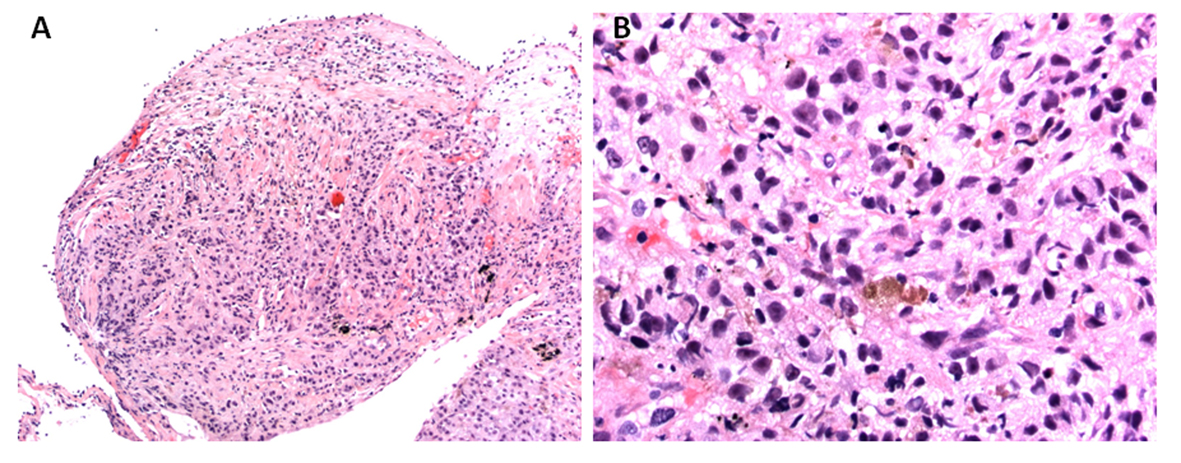

Given bilateral infiltrates and no significant cardiac dysfunction on echocardiogram, a diagnosis of ARDS was made. Moreover, his pO2/FIO2 ratio was less than 100 fulfilling Berlin criteria of severe ARDS definition [8]. An ARDS in the presence of lymphadenopathy, multiple pulmonary nodules as well as multifocal infiltrates conjure a broad differential. His bronchoscopy on eighth hospital day did not show any significant airway secretions or any mucosal lesions. Bronchoalveolar lavage revealed red blood cells of 76/mm3, white blood cell count of 850/mm3 neutrophil count 61%, lymphocytes 21%, monocytes 2%, and macrophages 6%. No malignant cells were seen. The bronchoalveolar lavage did not grow any virus, bacteria, fungus or mycobacteria. He received broad-spectrum antibiotics in form of vancomycin, azithromycin, pipercillin-tazobactam and micafungin without any significant improvement. Lymphoma has been uncommonly reported as causing ARDS but it is extremely unusual for melanoma to do so [9-11]. A lymphoproliferative disorder was excluded by flow cytometry of bronchoalveolar lavage. Subsequently on 12th day of admission, he underwent right upper lobe transbronchial biopsy (Fig. 4), which was positive for malignant epithelioid tumor, morphologically similar to malignant melanoma from his previous neck mass biopsy. Oncology was consulted for management of this patient’s melanoma. However, as per the oncologist’s opinion, no chemotherapy or biological agents could possibly improve his symptoms. Considering his very poor prognosis, the patient was transitioned to palliative care as per his family’s wish after 14 days of hospitalization.

![]() Click for large image | Figure 4. Histopathology of transbronchial biopsy from right upper lobe: (A) × 100 magnification and (B) × 400 magnification, showing malignant epithelioid cells with immunohistochemical staining positive for S100, Melan A and MITF, morphologically consistent with metastatic melanoma. |